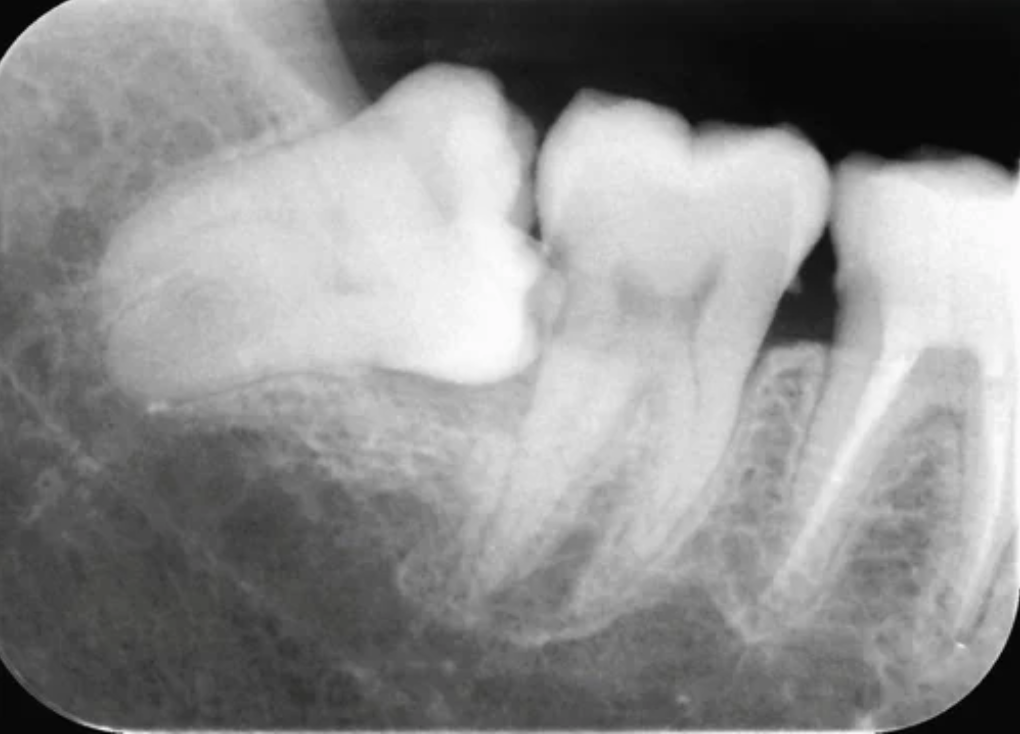

진단 및 검사

사랑니의 위치와 상태를 평가하기 위해 X-레이 촬영과 구강내 검진을 진행합니다.

납니다. 구강 내 공간이 부족한 경우 사랑니는 제대로 위치하지 못하거나 매복되

는 경우가 있습니다. 이런 사랑니의 경우 주변 치아의 손상을 일으키거나 주변 잇

몸의  통증, 염증의 원인이 될 수 있는데, 이런 경우 사랑니 발치가 필요할 수 있습

니다.